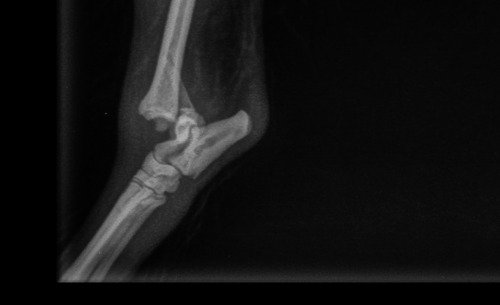

Ola eu sou o Simon de 7 aninhos e minha raça Sptiz Alemão. Sou muitooo traquina e peguei uma briga com meu irmãozinho porque estava com ciumes da minha mamãe humana. Torci, fraturei e rompi os ligamentos da minha patinha traseira a 10 dias atrás. Fui ao veterinário e o raio X constatou que meu caso é cirúrgico 😥. Estou com minha patinha imobilizada e sentindo fortes dores porque minha mamãe não esta em condições de arcar com a cirurgia que custa aproximadamente

R$ 4.000 isso inclui (exames, cirurgia, anestesia, pós cirúrgico e medicações)

Minha mamãe ja gastou bastante quando me machuquei e não tem mais recursos para realizar minha cirurgia e dar continuidade no meu tratamento

Conto com a ajuda de todos porque essa tal de fratura dói 😢